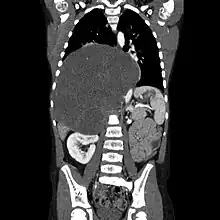

| CT scan of a large ganglioneuroma within the chest cavity | |